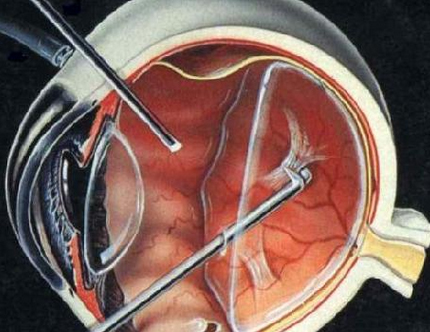

A:得了飛蚊症主要通過以下方法進行治療:1、藥物治療:藥物治療飛蚊症的療效不確切,飛蚊症又稱玻璃體混濁,可以分為生理性的玻璃體混濁和病理性的玻璃體混濁。對於生理性的玻璃體混濁,通常對患者的視力沒有特別的影響,一般不需要進行特殊治療,可以口服卵……

A:眼睛出現飛蚊,可以通過以下方法進行治療並緩解:1、藥物治療:藥物治療飛蚊療效並不確切,眼睛出現飛蚊又稱玻璃體混濁,可以分為生理性的玻璃體混濁和病理性的玻璃體混濁。生理性的飛蚊症,主要是由於隨著年齡的增加,玻璃體逐漸液化所導致,通常對患者的……